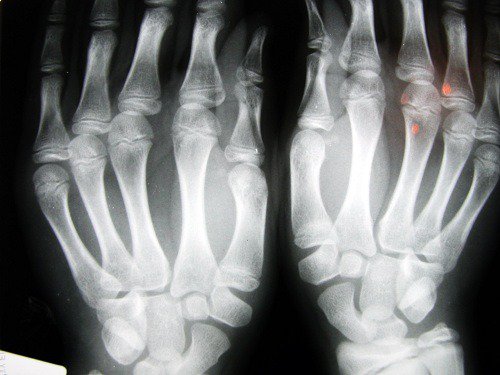

2. Ризик остеоартриту

Дослідження Ноттінгемського університету (Велика Британія) виявили, що люди з коротшим вказівним пальцем мають більше шансів на розвиток такого захворювання, як остеоартрит. Це пов’язують з нестачею естрогену та низькою фізичною активністю, що особливо негативно впливає на жінок.